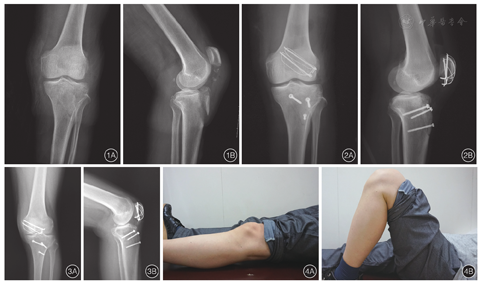

男性患者,50岁,从3 m高处坠落致左膝部疼痛、肿胀、活动受限4 h来我院就诊。患肢膝部肿痛明显,不敢伸膝及站立行走。既往无膝部外伤史,否认类风湿关节炎及化脓性关节炎病史。查体:左膝部肿胀明显,胫骨结节部压痛,伸膝时疼痛无力。影像学检查诊断为左胫骨结节撕脱骨折合并髌骨下极撕脱骨折(图1A,B)。鉴于患者胫骨结节骨折移位明显,保守治疗难以复位,效果不佳,遂于入院后7 d在蛛网膜下腔阻滞麻醉下行左胫骨结节撕脱骨折、左髌骨下极撕脱骨折切开复位内固定术。

患者取仰卧位,麻醉满意后取膝关节前方正中切口,依次切开皮肤和深筋膜,暴露髌韧带及胫骨结节,可见骨折片自胫骨结节连同胫骨近端少量骨质向近端延伸至胫骨平台前缘,未累及胫骨平台关节面,撕脱骨折块受髌韧带牵拉向近端移位,旋转移位不明显。伸直膝关节,复位骨折,应用3枚空心螺钉固定,使用髌钳复位髌骨下极骨折,并用张力带固定(图2A,B)。屈伸膝关节检查见骨折片固定牢固,无移位。缝合伤口,2周后拆线,伤口甲级愈合。术后即指导患者进行膝关节功能锻炼,患侧膝关节活动范围可达到0~120°。术后6个月随访,X线片示胫骨结节及髌骨下极骨折一期愈合(图3A,B),患者膝关节伸屈活动度良好(图4A,B),已回到伤前工作岗位工作。